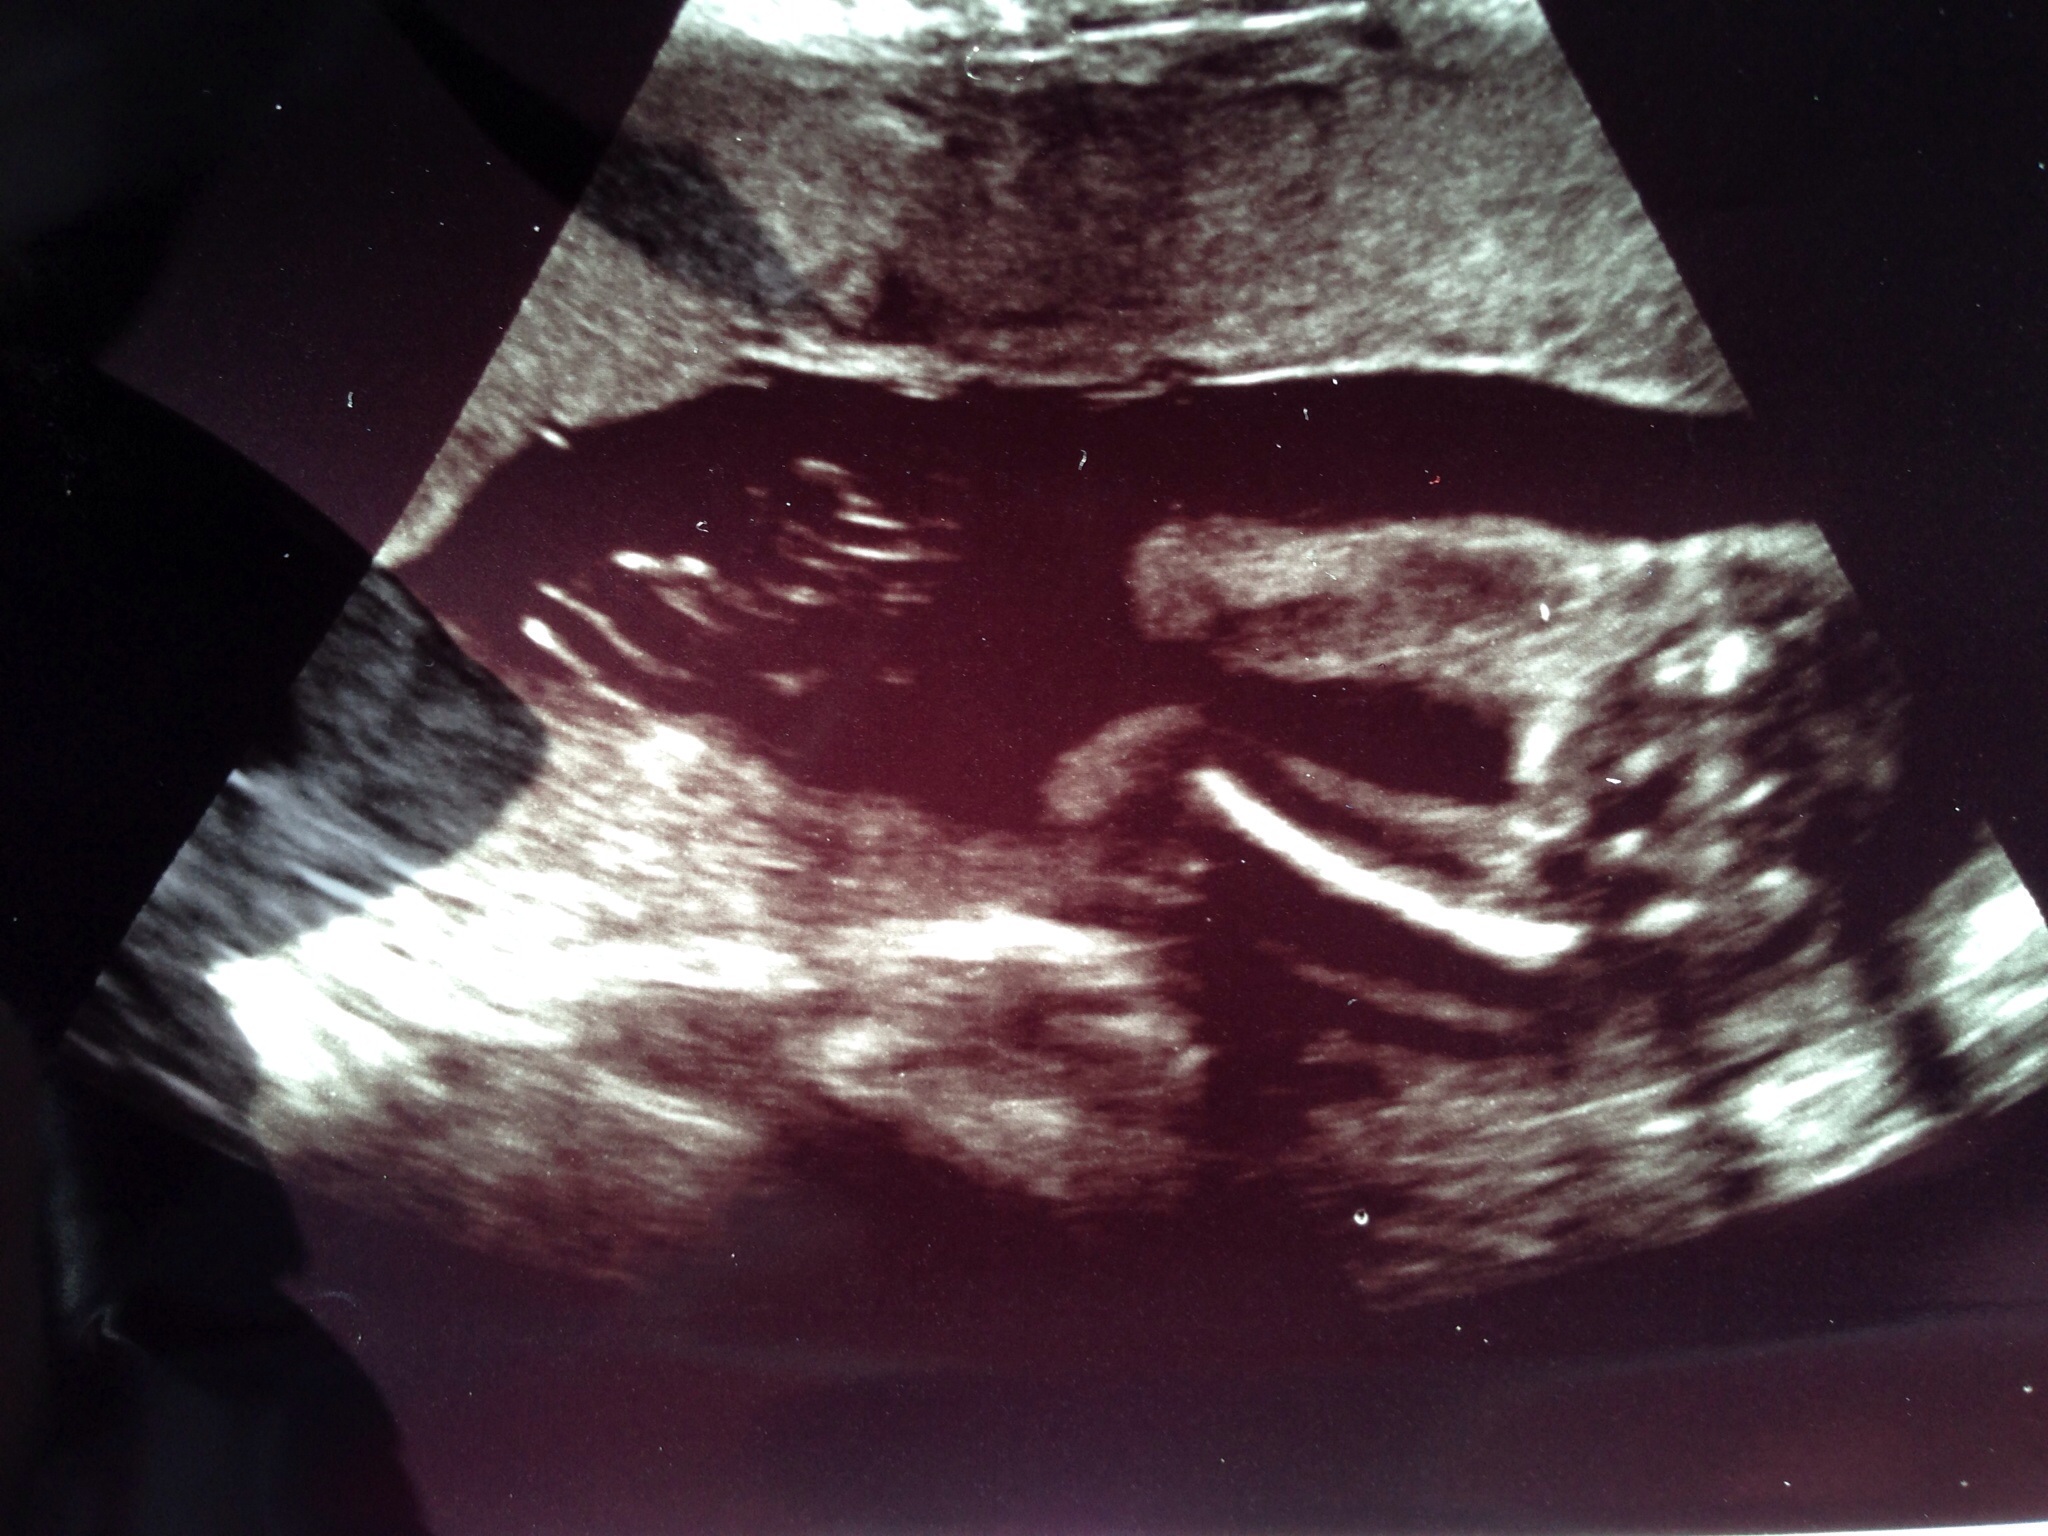

Attachment 24598

Definite girly bits. Congrats!

Girl

Girl.